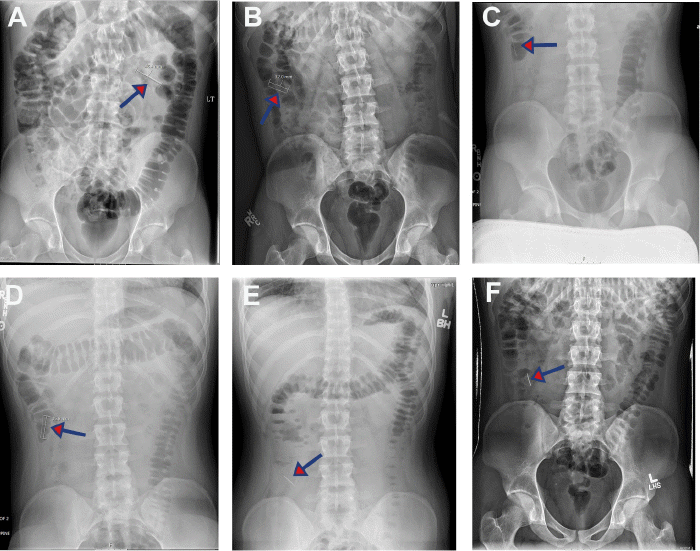

Figure 1. CXR and KUB Demonstrating Needle Visualization and Transit Through Patient's Upper GI System Over Time. Published with Permission

On initial CXR, the lungs were found to be clear with no infiltrate, edema, or effusion, and the heart and mediastinum were within normal limits. A needle measuring approximately 41 mm was visualized (A-B, arrow) shortly after presentation and presumed to be in the stomach. KUB shortly after revealed no dilated bowel or obstruction, organomegaly, fracture, or abdominal calcification, but did reveal the needle in the left upper quadrant, presumably moved into the distended stomach or within the duodenum (D)

Figure 3. Sequential KUB Imaging Reveals Needle Transit Through Small Bowel. Published with Permission

Sequential KUB images were acquired at approximately (A-B, arrow) 16, (C-E, arrow) 36, and (E, arrow) 48 hours post-presentation, which revealed movement of the needle from early segments of the small bowel presumably to the ascending portion of the colon